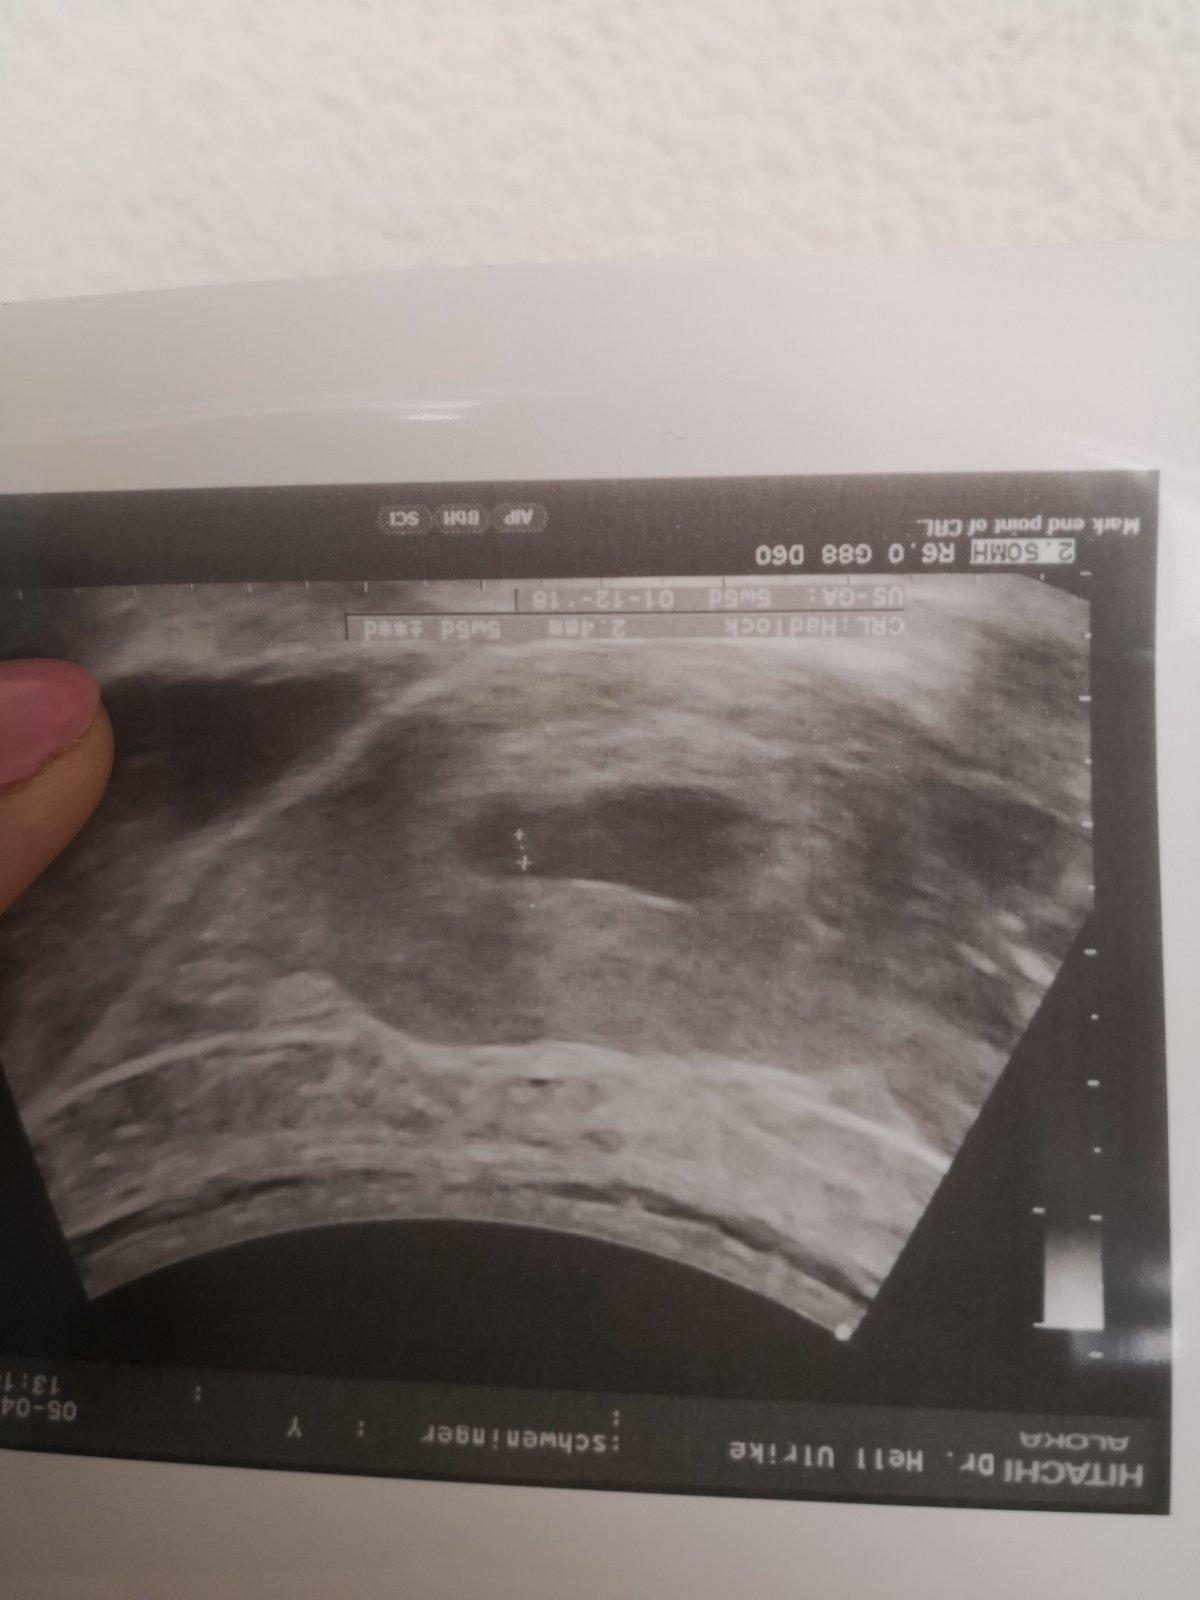

@luta13 ahoj nove info... Dnes som mala kontrolu som 6+1 srdiecko mame a 3mm.vsetko je ok.kontrola o tyzden... Tak hadam to dame tentokrat